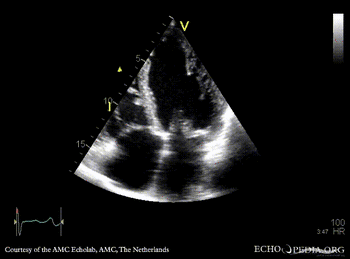

A4CH: Color Doppler, severe mitral regurgitation, excentric jet Continuous-wave signal of tricuspid regurgitation, increased systolic pulmonary artery pressure